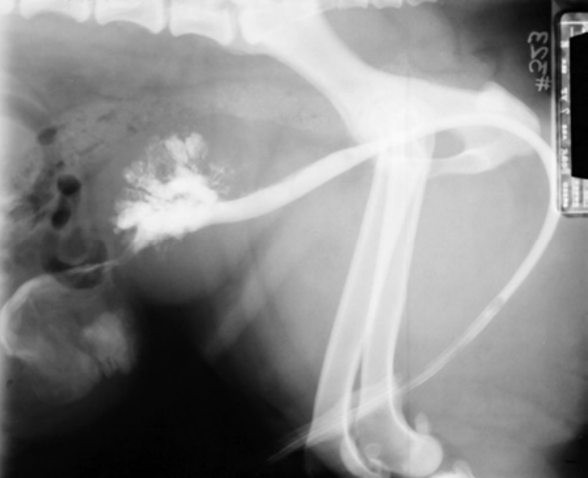

| Contrast radiography _Pyelonephritis | (contrast = ์กฐ์์ ์ฌ์ฉ) |

|---|---|

![]() | - Mild to moderate pyelectasia (์ ์ฐํ์ฅ) - Distortion of renal pelvis (์ ์ฐ ๋ณํ) |